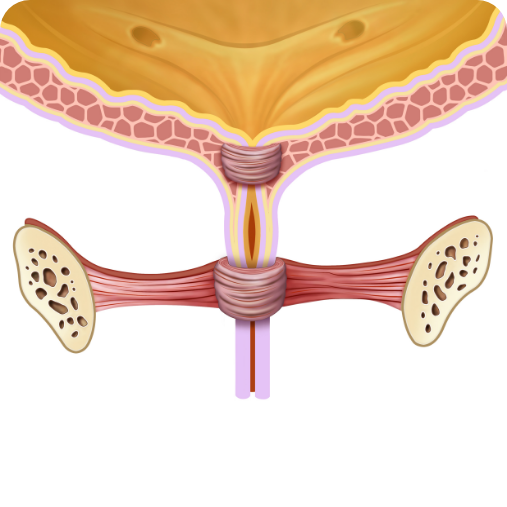

PRZED kuracją:

Słabe mięśnie cewki

PO kuracji:

Mocne mięśnie cewki